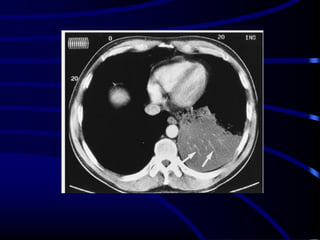

This is the same concept

as a silhouette sign. If

you can recognize the

interlobar pulmonary

artery, it means that the

mass seen is either in

front of or behind it.

This is an example of a

dissecting aneurysm.